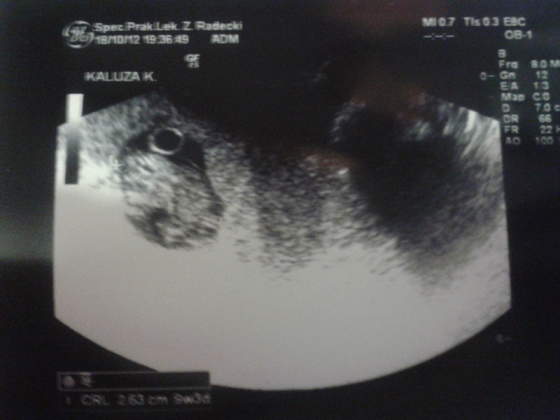

Ja tez po wizycieDzidzius ma 2,36cm i serduszko 170 uderzen na min

) Z USG wychodzi 9w3d

A to moj dzidzius zwiniety w fasolke - ale ruszal sie bo doktorkowi tetno uciekalo hehe))

Zobacz załącznik 508495